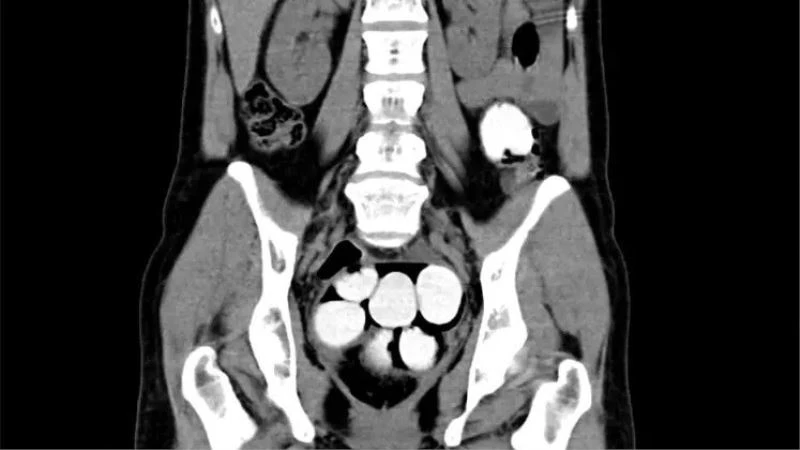

Yolcunun üzerinde ve valizinde herhangi bir uyuşturucu maddeye rastlanmazken, yolcu detaylı kontrol için hastaneye götürüldü. Hastanede, tomografi cihazı ile yapılan kontrollerde yolcunun midesinde yüksek yoğunluğa sahip kokain dolu 124 adet kapsül tespit edildi.

Prag Vaclav Havel Havaalanı Gümrük Sözcüsü Sarka Miskovska yaptığı açıklamada, “Rutin risk analizi kapsamında yaptığımız kontroller sırasında uyuşturucu testi pozitif olan bir yolcu ile ilgili yaptığımız detaylı inceleme sonrasında 124 kapsülden oluşan bin 429 gram yoğunlaştırılmış kokain ele geçirdik. Bu tarz taşıma şekli zor yakalanabilen fakat taşıyan için de bir o kadar riskli olan bir yöntem. Kapsüllerden birinin bağırsaklarda patlaması durumunda aşırı doz uyuşturucudan ölüm gerçekleşebilir” dedi.